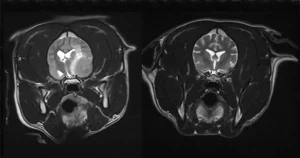

The Labrador was urgently referred to Bristol Vet Specialists’ neurology team, where an emergency MRI scan revealed a large mass in the left side of her brain.

A three-month MRI revealed the Labrador’s tumour had completely vanished.

Eight months after her diagnosis, Purdey has just had another MRI come back entirely clear.